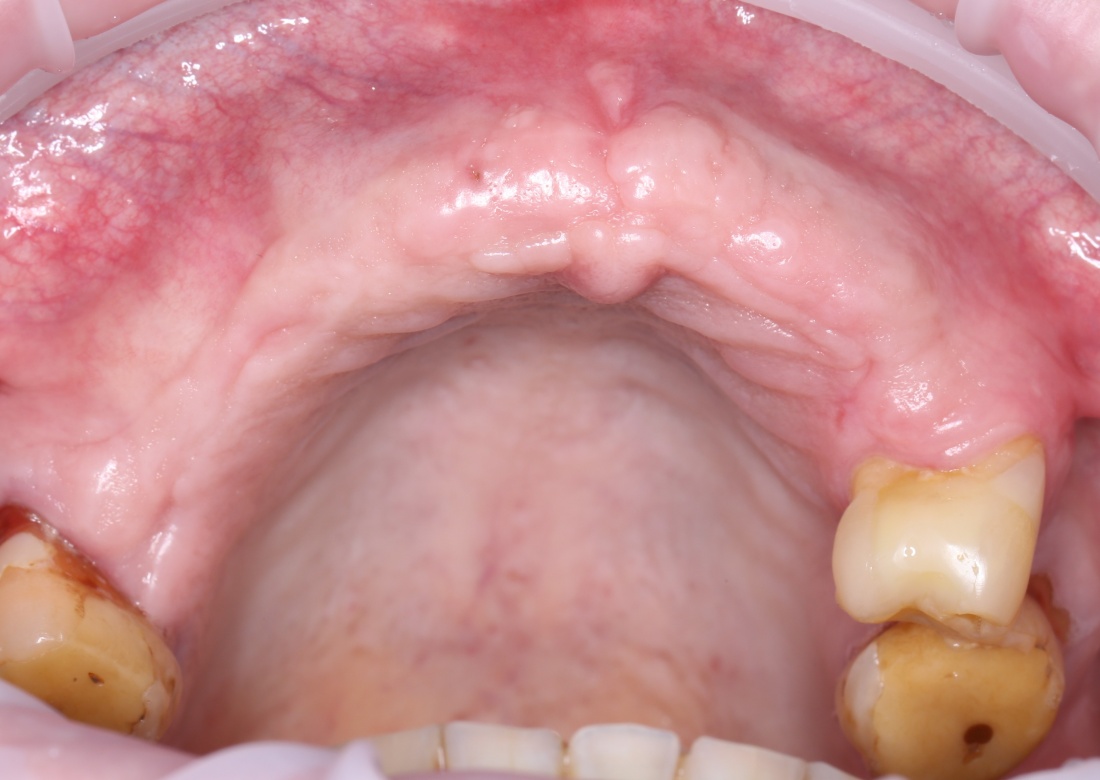

Вот клиническая картина через 4 месяца после ранее проведенной имплантации с остеопластикой:

Как видишь, коллеги из недалекой дружественной страны не осилили снятие швов. Мне это не нравится, хотя и объясняет, почему люди готовы ехать за тыщи километров ради 20-минутной операции удаления зуба мудрости.

Ну хорошо. Швы сняли. Делаем разрез. Обрати внимание, что после всех проведенных операций у нас остается очень небольшой по ширине слой жевательной слизистой оболочки: